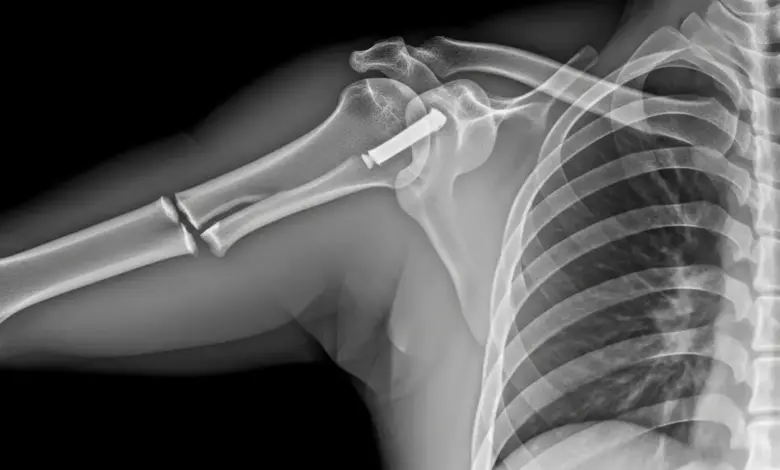

Fraturas na região do ombro acontecem, na maioria das vezes, no úmero proximal e na clavícula. A escápula entra como causa mais rara e, quando aparece, geralmente vem associada a traumas mais fortes.

Fraturas complexas do úmero proximal, fraturas expostas, fraturas associadas a lesões vasculares ou neurológicas e casos em que o alinhamento não se mantém durante o seguimento clínico entram nesse grupo.

Em pacientes idosos, algumas fraturas demandam próteses específicas, já que a fixação com placas e parafusos pode não oferecer estabilidade suficiente devido à qualidade óssea.

Exames de imagem, como radiografias em múltiplas incidências e tomografia computadorizada, ajudam a compreender o padrão da fratura e a planejar o tratamento.

O procedimento cirúrgico varia conforme o tipo da fratura. As técnicas incluem fixação com placas e parafusos, fios metálicos, pinos ou substituição parcial da articulação por prótese em casos selecionados.